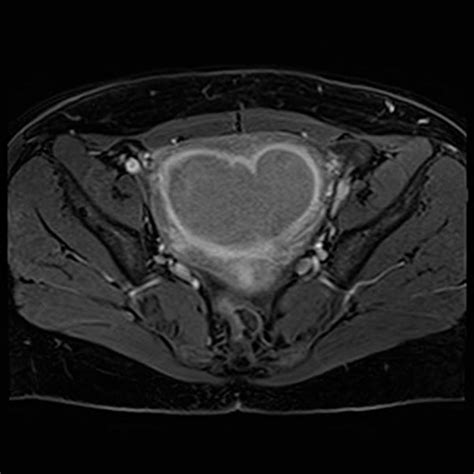

Uterus - Leiomyoma - NUS Pathweb :: NUS Pathweb

2010×1136